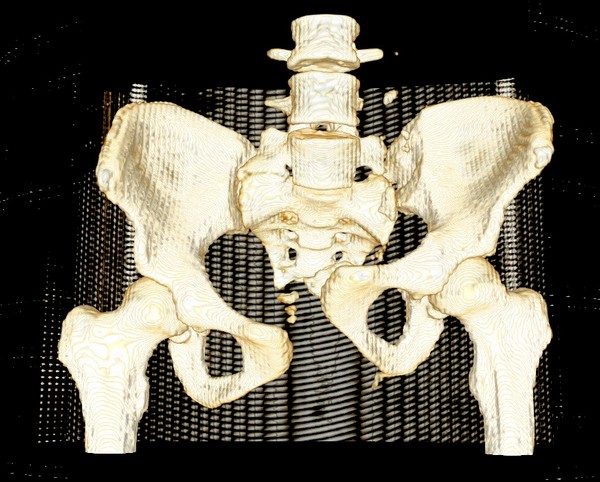

Девочка 14 лет. Кататравма (падение с высоты 4-5 этажа). Вертикально нестабильный перелом таза со смещением, разрывом лонного и левого подвздошно-крестцового сочленения, перелом крестца, открытый перелом костей голени. Ребёнок оперирован на 10-е сутки после травмы - выполнили максимально возможную репозицию на ортопедическом столе, синтез лонного сочленения реконструктивной пластиной (из имеющихся пластин - на 7 дыр - самая длинная, получилось только по 2 шурупа с каждой стороны, поэтому пришлось подстраховаться проволокой), АВФ. Задний комплекс не фиксировали ввиду отсутствия канюлированных (да и неканюлированных)шурупов должной длинны.В настоящий момент перед нами стоит вопросов:1. Обязательно ли фиксировать подвздошно-крестцовое сочленение, либо фиксации АВФ будет достаточно? Аппарат стоит достаточно стабильно, девочка при перемещениях в пределах постельного режима болевых ощущений не испытывает.2. Что делать с отломком крестца, который довольно значительно смещён кпереди? В настоящий момент никаких проблем с дефекацией у больной нет, хотя, глядя на КТ, создаётся впечатление, что отломок прямо-таки лежит на прямой кишке. Репонировать-фиксировать? Просто удалить? Вообще не трогать? Не создаст ли он в дальнейшем проблем во время родов?Хотелось бы знать мнение уважаемых коллег.Заранее спасибо.